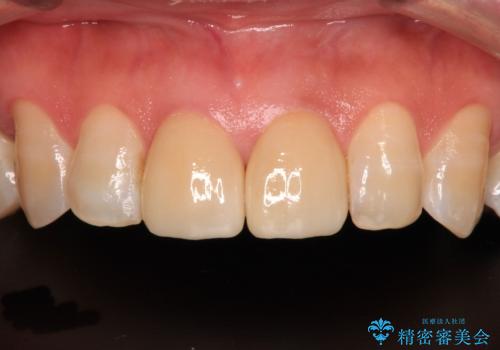

統一感のあるきれいな色調となり、患者様には大変満足していただきました。